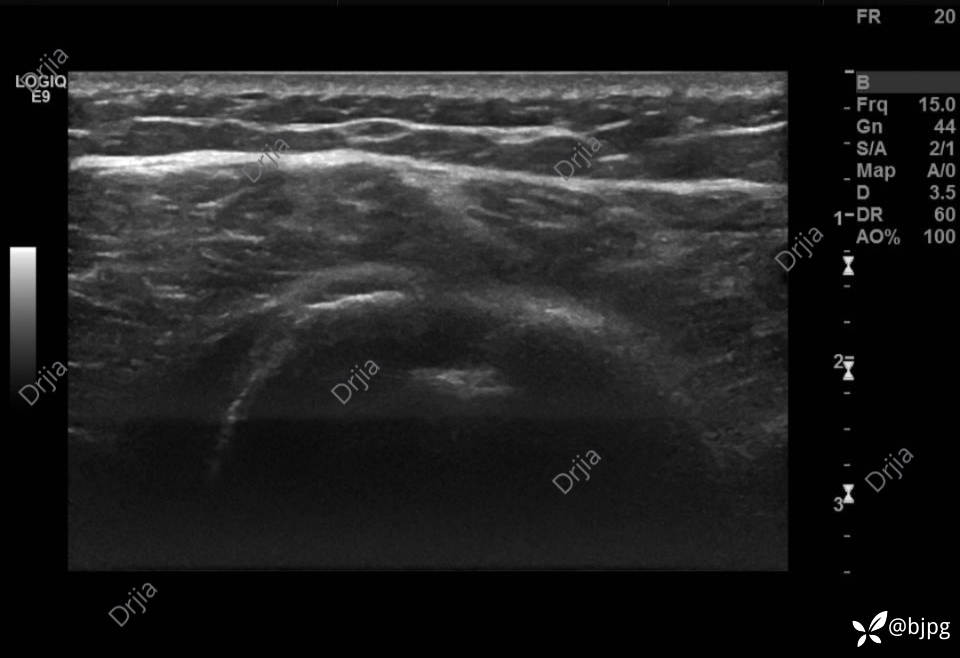

患者女性,48岁,左上臂肿物1月就诊。

1月前发现左上臂肿物,无疼痛,无明显功能障碍。今日就诊,行左上臂肿物超声检查:

左侧结节间沟空虚

沿肱二头肌走行区纵切扫查未见肌腱影像

肱二头肌肌腹圆钝,腱腹移行消失

肱二头肌远心端断端血肿形成